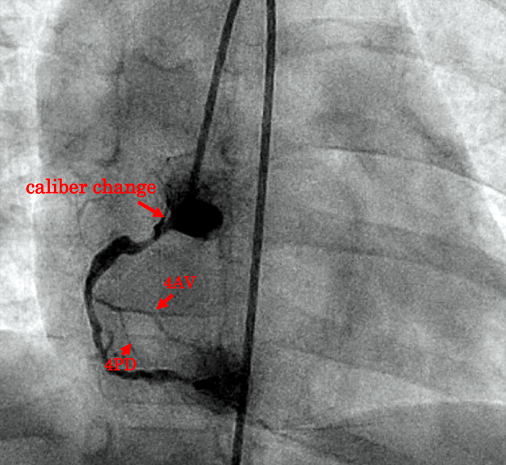

Fig. 1 RCA angiography

(a) The coronary artery fistula is from the RCA to the LV. The RCA is markedly dilated (7.3 mm). (b) A lateral view shows the course of the fistula from the RCA to the opening in the LV. (c) With the fistula temporarily occluded, the normal course of the RCA was identified. The so-called 4AV and 4PD are clearly visualized. (d) The AVP has just uncovered. Contrast medium was injected repeatedly through the guiding sheath in order to confirm the optimal site of device implantation. AVP, Amplatzer™ Vascular Plug II; 4AV, #4 atrioventricular branch; 4PD, #4 posterior descending branch; LV, left ventricle; RCA, right coronary artery.

Secondly, a 4 Fr wedge pressure balloon catheter (Alpha Medical Instruments, LLC., CA, USA) was advanced from the LFA into the RCA over the wire loop. We repeated test balloon occlusion in order to identify an appropriate site for embolization without ST changes on electrocardiogram. RCA angiography illustrated the fistula distal to the posterior descending branch (4PD) (Fig. 1c) when the fistulous communication was test occluded. We decided to close the channel distally to the origins of the 4PD and the posterior atrioventricular branch (4AV), and paid attention to avoid protrusion of an occluder into the LV cavity. The maximum vessel diameter of the site was 6.8 mm. Use of coils did not appear appropriate, and we chose a 10-mm-diameter AVP II in the long and large segment.

A short sheath at the RFA was removed. We advanced a 5 Fr flexible guiding sheath (Flexor® Ansel Guiding Sheath No. 2, Cook Medical Japan G.K., Tokyo, Japan) anterogradely to the distal end of the embolization site. Then, an AVP II was deployed there. We repeated angiography through the guiding sheath to prove that the device was at the optimal embolization site (Fig. 1d). We detached the AVP II after confirming no ST changes noted on electrocardiogram, no obstruction of the branches of the normal coronary artery on repeated angiography, and no mitral regurgitation or stenosis on transthoracic echocardiography. Angiography after implantation showed only a small residual shunt. No complications occurred.